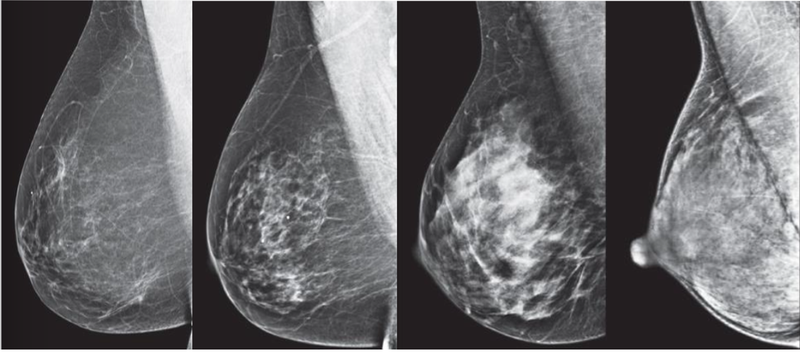

Mật độ mô vú (hay còn gọi là mật độ nhũ ảnh) là một thuật ngữ y khoa được sử dụng để mô tả hình ảnh vú trên phim chụp tuyến vú để đo các loại mô vú khác nhau.

Mật độ mô vú (hay còn gọi là mật độ nhũ ảnh) mô tả hình ảnh vú trên phim chụp tuyến vú 1 Mật độ mô vú (hay còn gọi là mật độ nhũ ảnh) mô tả hình ảnh vú trên phim chụp tuyến vú

Mật độ mô vú rất quan trọng vì nó có thể có tác động nghiêm trọng trong việc chẩn đoán ung thư vú. Phụ nữ có bộ ngực không đều hoặc cực kỳ dày (Loại C và D trên thang điểm BI-RADS) có nguy cơ mắc ung thư vú cao hơn so với phụ nữ có bộ ngực trung bình và nhỏ.

Các tuyến vú và mô liên kết có thể che giấu bệnh hoặc gây nhầm lẫn, khiến việc phát hiện sớm bệnh ung thư trở nên khó khăn. Điều này là do tế bào ung thư, mô tuyến và mô liên kết đều có màu trắng trên phim chụp quang tuyến vú. Theo đó, các mô khỏe mạnh có thể che giấu tế bào ung thư.

Phụ nữ có bộ ngực dày (lớn) có nhiều nguy cơ bị chẩn đoán sai bệnh ung thư, và do đó, họ bỏ lỡ giai đoạn phát hiện ung thư sớm ở các lần chụp quang tuyến vú. Các bác sĩ thường phát hiện bệnh khi bệnh nhân có các triệu chứng như có khối u, tiết dịch ở núm vú. Do bị phát hiện muộn, họ mất nhiều thời gian điều trị hơn, nhưng kết quả có thể không khả quan.